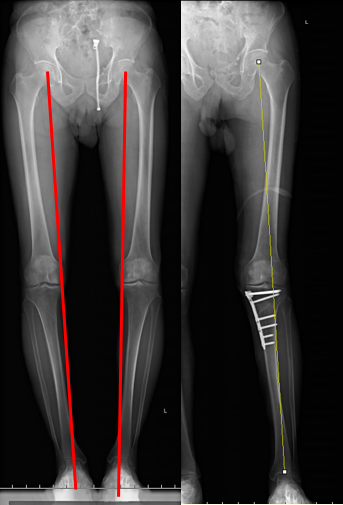

图1:该患者为左侧膝骨关节炎晚期,膝关节内翻畸形

在选择治疗方式前,我们首先需要照双下肢全长负重位正侧位X线片和髌骨30°轴位X线片,可以判断是关节内畸形还是关节外畸形;必要时加照膝关节内翻或者外翻应力位正位照片,查明是膝关节内侧或者外侧软骨退变的轻重和部位。膝关节磁共振检查对于诊断半月板退变、撕裂和脱位及评估软骨的厚度方面具有一定的价值。

膝骨关节炎的患者80%会累及到膝关节内侧的软骨,表现膝关节内侧疼痛,内翻畸形等。如果患者年纪轻,具有一定的活动要求,且软骨退化并不是很严重时,可以选择胫骨高位截骨术,完全保留膝关节的韧带和半月板,通过调整力线,释放内侧关节软骨的压力,达到缓解疼痛的目的,是一种真正的保膝手术。

68岁阿叔,左膝关节疼痛2年了,他的要求是希望手术后除了不痛,还要求以后可以踢毽子和游泳,考虑到他膝关节内侧软骨磨损并不是完全磨损,结合他个人的手术期望值,治疗方式为:胫骨高位截骨术,术后第二天就下地行走,术后一个月完全恢复正常,非常满意